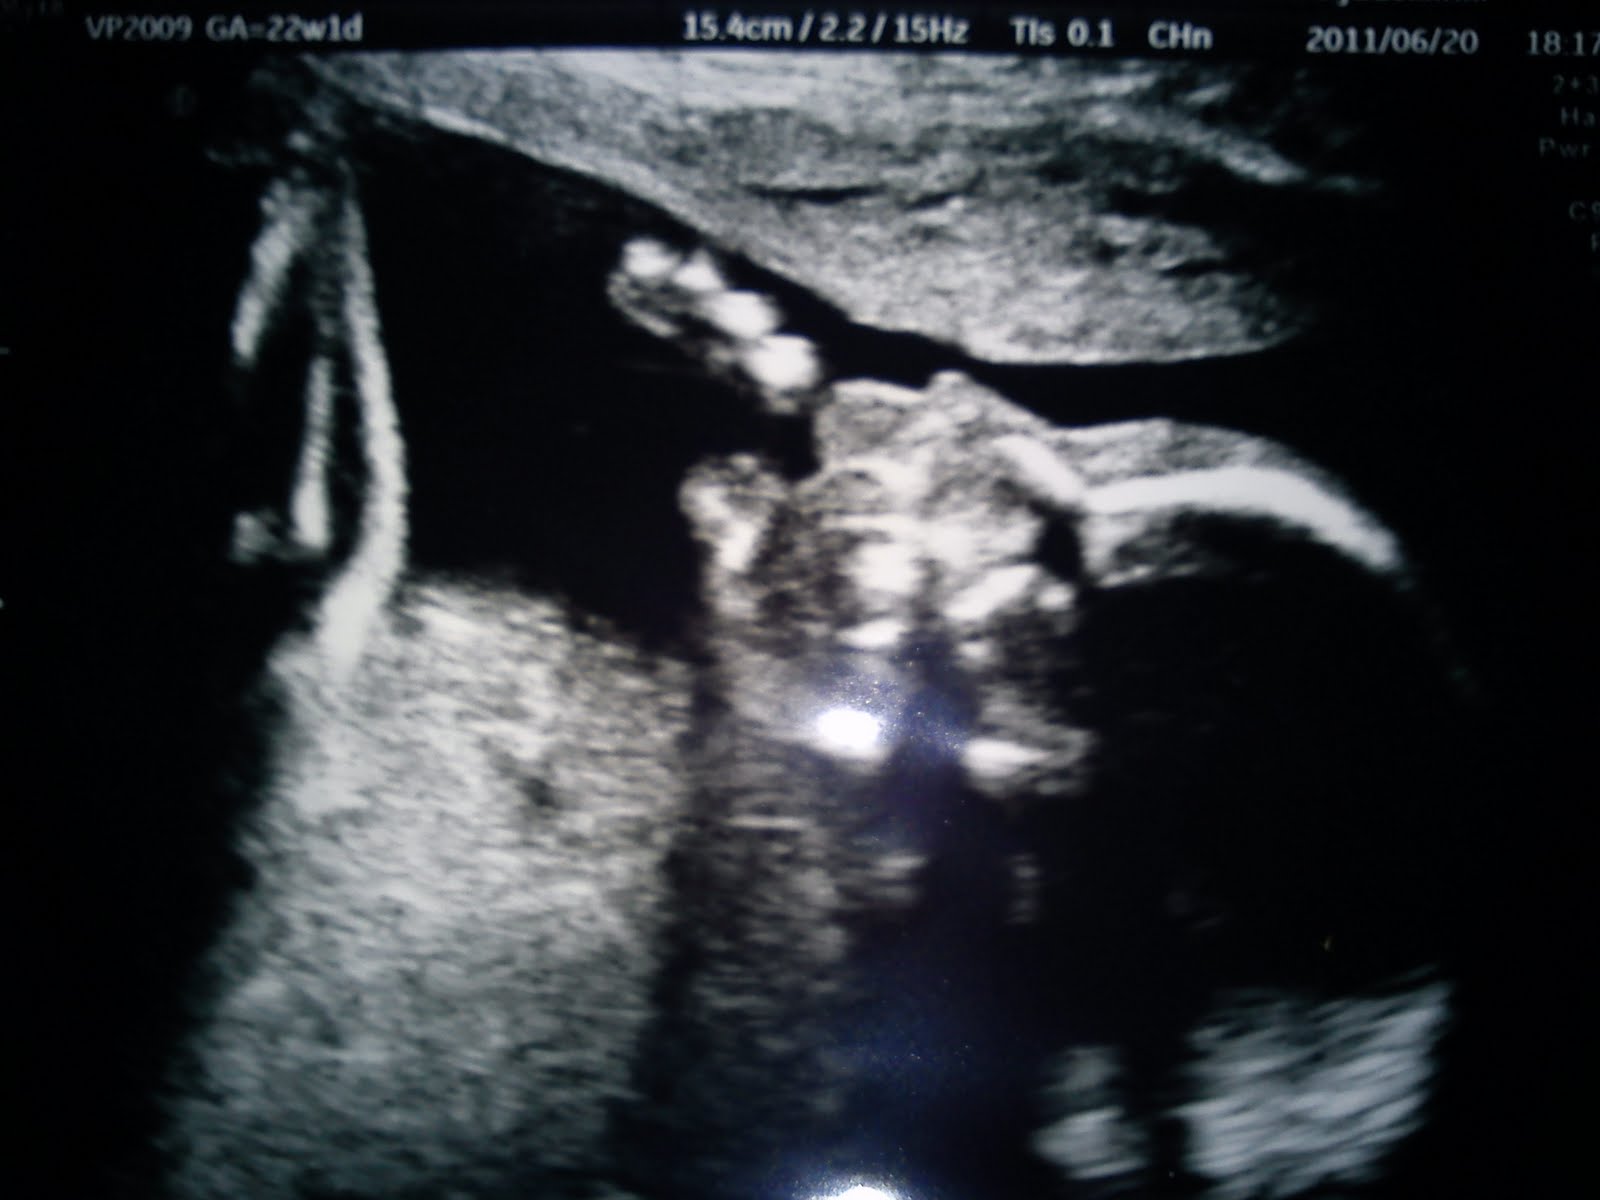

Ja idag va det ul 18.00 i gbg på Emma ultraljudskliniken o allt var så bra så! Åh mycket bättre bilder denna gången (nio vanliga o en i 3D).

När hon sa att det va en pojk och här har vi snoppen så säger Morgan: Se, jag sa ju att jag såg en snaaling på för ultraljudet! Haha!

Här e en av bilderna iaf:)